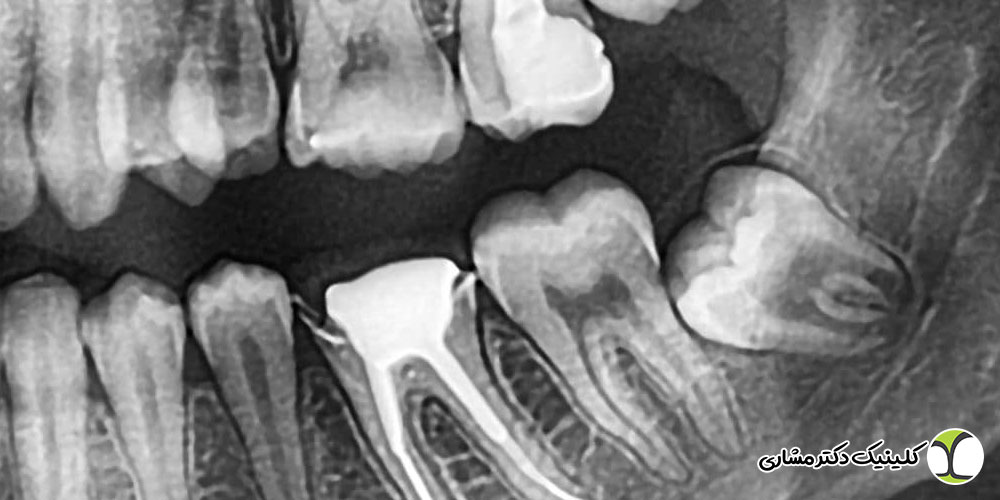

- پر کردن ریشه و ترمیم نهایی

پس از اطمینان از پاکسازی کامل کانالها (که اغلب با کمک تصاویر رادیوگرافی تأیید میشود)، ریشهها با مواد مخصوصی (مانند گوتاپرکا) که از ورود مجدد باکتریها و عفونت جلوگیری میکنند، به طور کامل پر و مسدود میشوند. مهر و موم شدن کامل ریشه برای جلوگیری از نفوذ مجدد میکروبها حیاتی است. در نهایت، تاج دندان با مواد مناسب یا در صورت لزوم با روکش دندان ترمیم میشود. این ترمیم نهایی ضروری است تا دندان عصبکشی شده از شکستگی محافظت شود و بتواند عملکرد خود را در جویدن به نحو مطلوب حفظ کند. ترمیم بهینه، عمر مفید دندان درمان شده را به میزان چشمگیری افزایش میدهد.

تصمیم نهایی برای درمان ریشه یا کشیدن دندان عقل، یک تصمیم چندعاملی است که تنها پس از معاینه دقیق رادیوگرافی و بالینی توسط متخصص درمان ریشه (اندودونتیست) اتخاذ میشود. اگر دندان عقل فضای کافی داشته باشد، در راستای صحیح باشد و از نظر عملکردی مفید باشد، درمان ریشه یک گزینه عالی برای حفظ آن به شمار میرود.